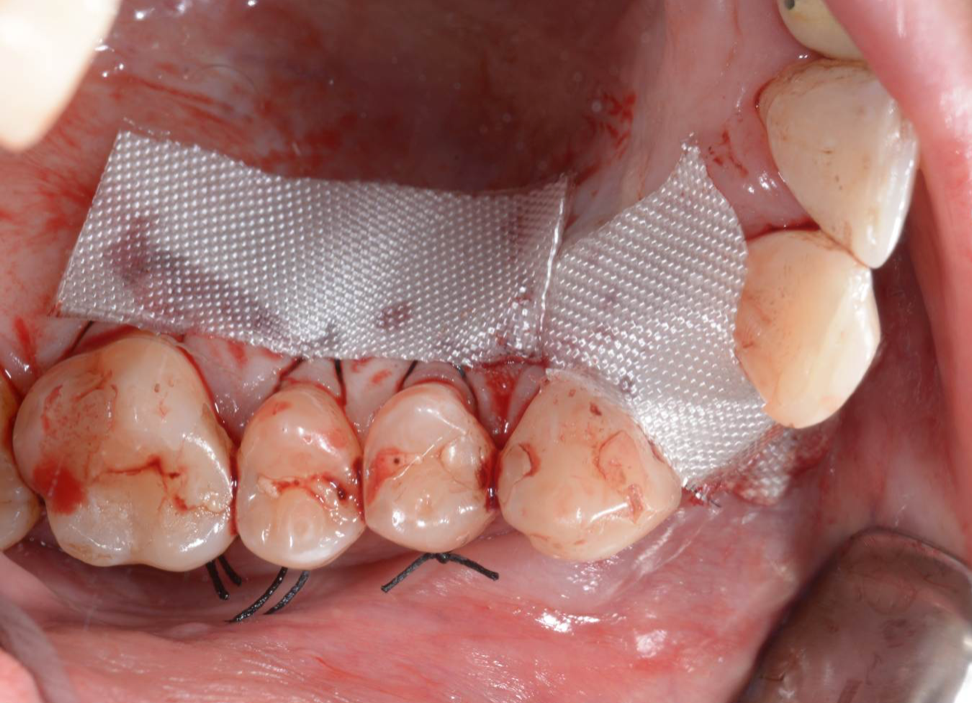

Während oder nach oralen Operationen, von der Extraktion von Zähnen bis hin zu rekonstruktiven Eingriffen, oder Implantationen, bietet BloodSTOP® iX eine schnelle und vorübergehende Kontrolle von Oberflächenblutungen.

BloodSTOP® iX absorbiert schnell Blut und verwandelt sich in ein klares Gel, um die Wunde mit einer transparenten Schutzschicht zu versiegeln, Blutplättchen zu binden und zu aktivieren, sowie die Gerinnung und Wundheilung zu unterstützen.

Anwendungsbeispiele

- Parodontale und chirurgische Wunden